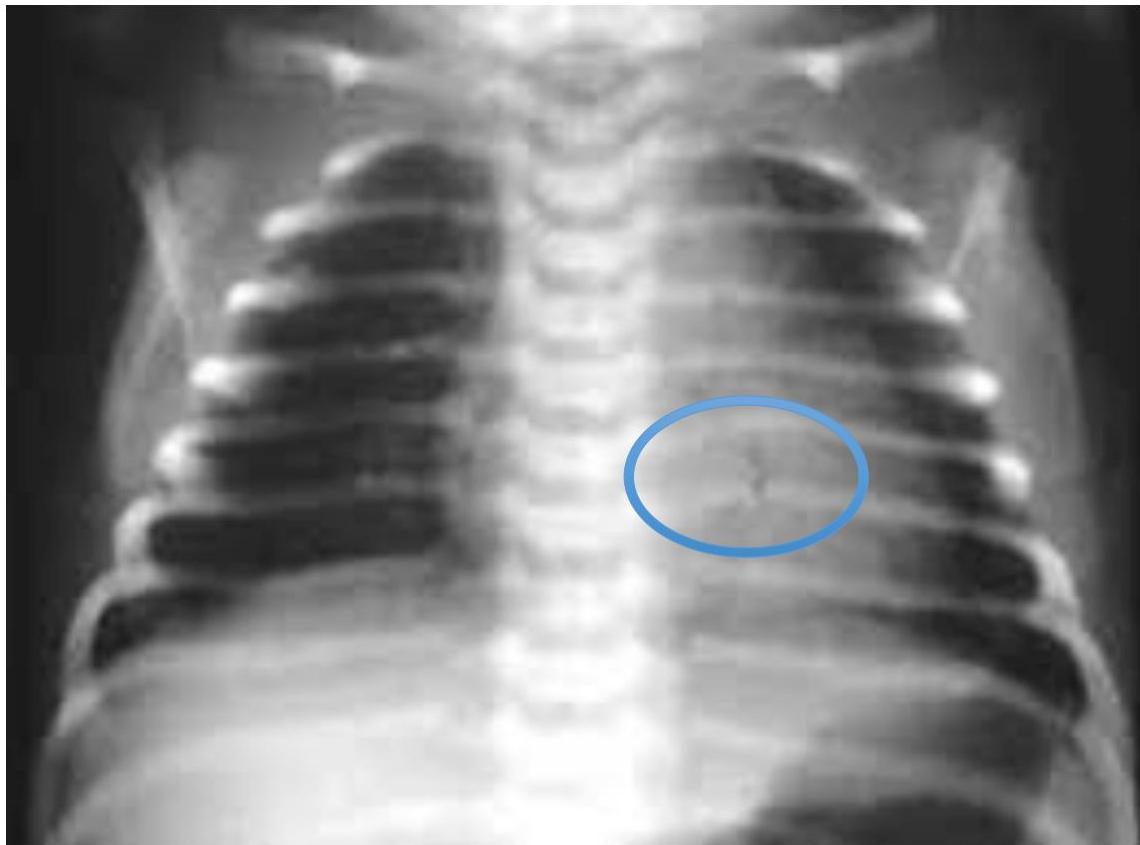

Asthma with Pneumothorax / Emphysema (CXR)

in This PIC Be Curfiat → Check Countage of the lung

Hint: Loss of contour of lung

- Check if hyperinflated

The hint is loss of Couture of lung in the emphysema → we doubt see?

Scenario: 5 year old with 3 days of acute asthma, progressive SOB, cyanosis.

CXR findings?

- Right-sided pneumothorax (or horizontal pneumothorax), subcutaneous emphysema, with left mediastinal shift

- Loss of lung opacity

- Mucous plug causing collapse/obstruction